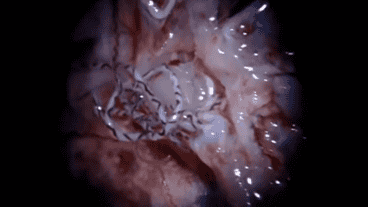

El angiostrongylus cantonensis accede al organismo humano a través de la ingesta de caracoles y ranas infectadas. Entre los síntomas se encuentran dolores fuertes de cabeza, fiebre alta, náuseas, vómitos y parálisis de músculos faciales o de extremidades y según las autoridades sanitarias es imposible eliminar a esta especie una vez que ingresó al cuerpo humano.